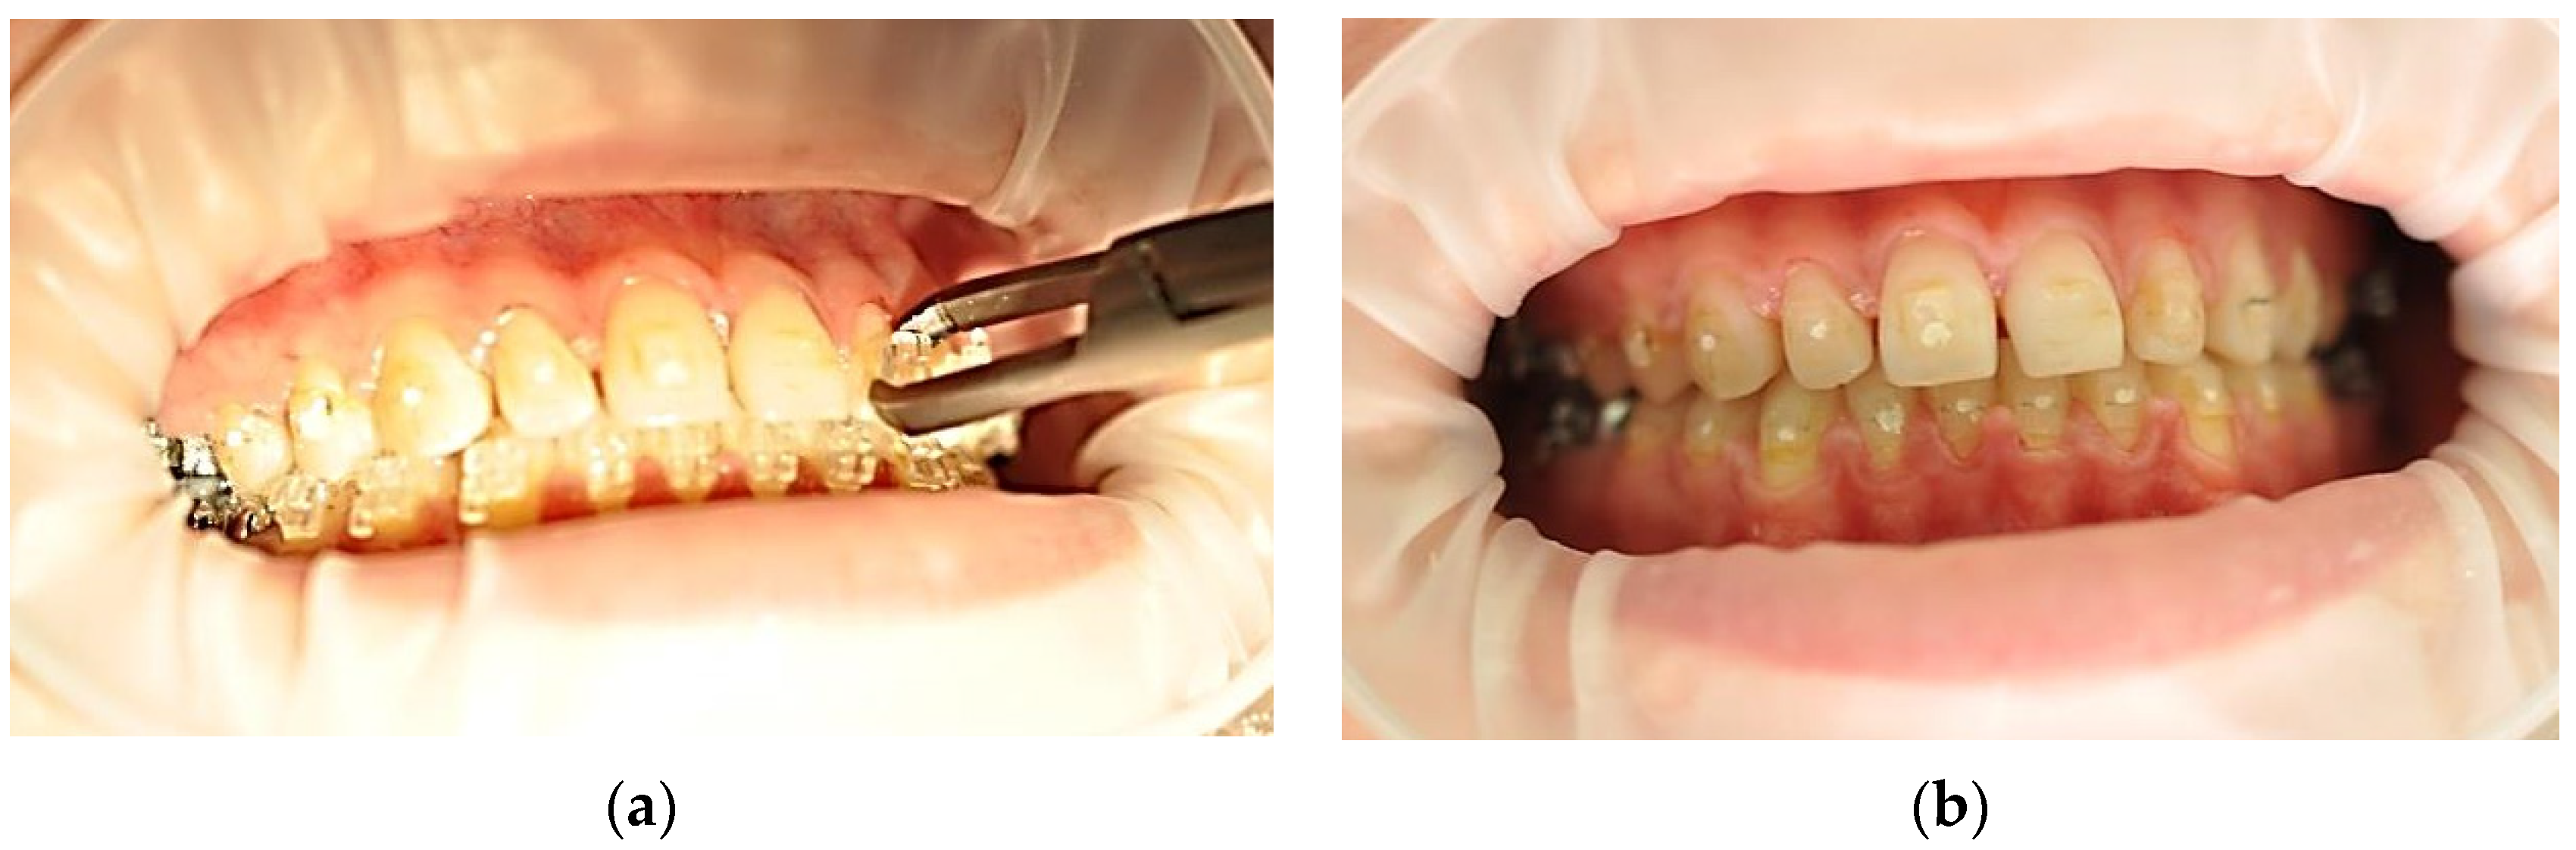

2.3. Debonding Systems

2.5. The Working Technique

2.6. Data Analysis